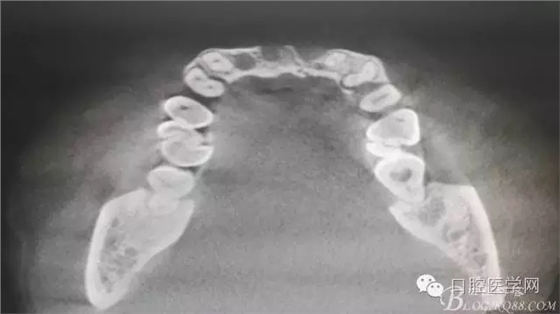

為他院轉(zhuǎn)診患者。男,無(wú)吸煙史,前牙因齲壞治療后,外力折斷導(dǎo)致拔除?,F(xiàn)拔除該牙后兩個(gè)多月。 左上區(qū)域骨寬度不足,計(jì)劃植入種植體同期GBR。

左上區(qū)域骨寬度不足,計(jì)劃植入種植體同期GBR。

植入種植體左側(cè)3510,右側(cè)4010,植骨Bioss,蓋膜Cytoplast。骨膜減張垂直褥式縫合加間斷縫合。